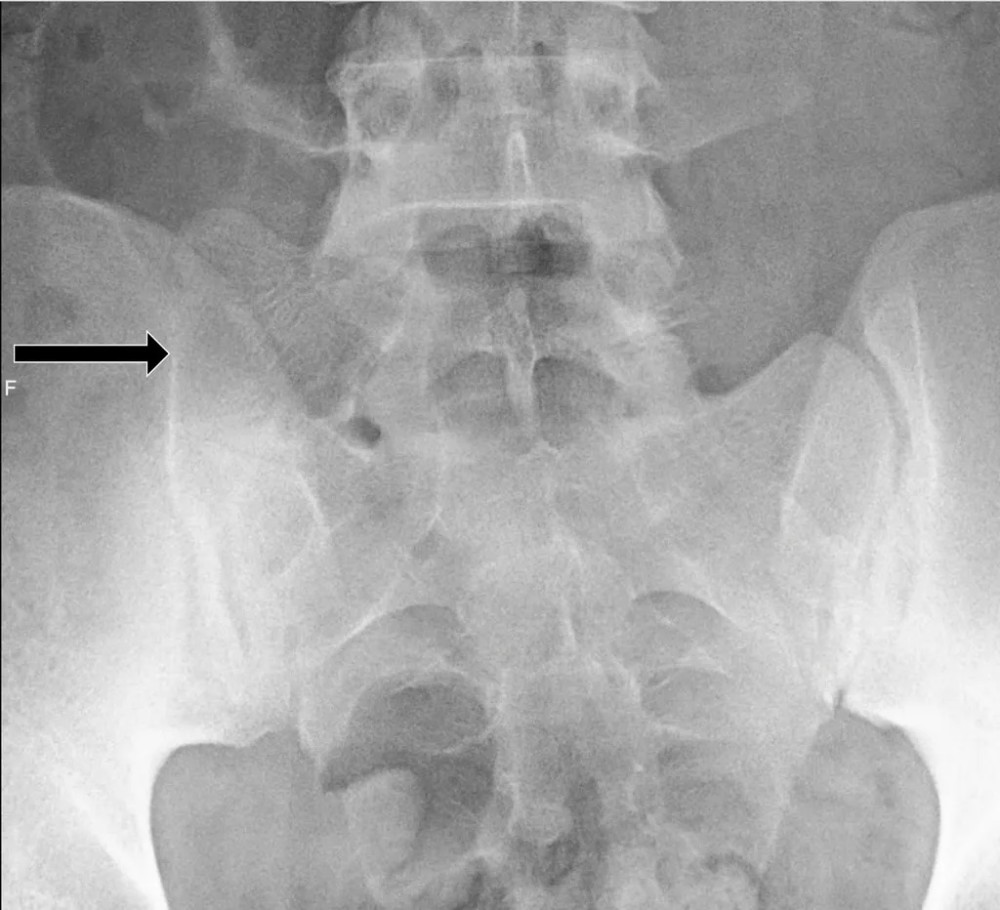

文章插图

L5 双侧横突肥大 , 间隙变窄 , 假关节形成 , 为 Ⅱb 型;

L5 椎体右侧横突肥大与骶骨发生骨性融合 , 为 Ⅲa 型;

黑色箭头所指处为骨性融合处